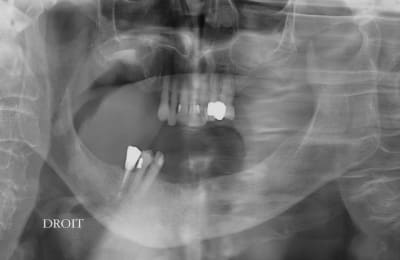

la patiente à eu deux mobiles en 6 mois,(pas par moi) elle ne les supporte pas, elle veux d'abord le bas, je prepare le haut de façon simple, je me plante sur le sinus gauche, je gérerais plus tard (je ne peux pas aller plus vite que la musique) et j'essaie de lui faire un bas fixe ce qui n'est pas evident sur un pano c'est l'epaisseur de l'os

pour une fois je pense utiliser des implants courts (- de 10mm) donc j'en mets plus que des longs.

le sinus présenté etait une occasion de "préparer" le site avec le système "balloon" de Meissinger qui m'etait prété en démo, et je ne suis pas satisfait du résultat obtenu car il est difficile de manipuler un interieur de sinus sans visibilité

l'idée me plaisait, pas la réalisation.

J’en reviens au fait que j'ai mis sur nonol un cas de sinus fait au balloon, c'est ce qui me paraissait important, et que la discussion s'étale sur la planification du travail.

Mais il me semblait important de dire que le système balloon était très praticien dépendant et ne m'a pas semblé être un progrès ni une simplification par rapport aux méthodes que j'utilise d'habitude.